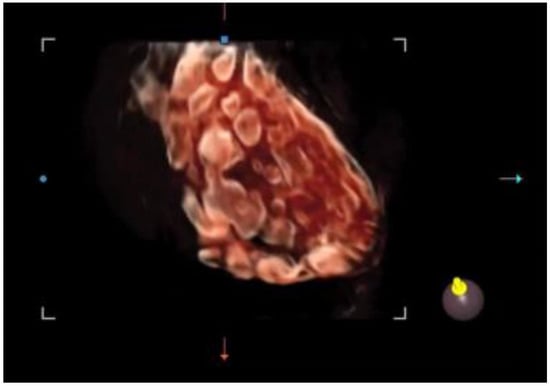

It offers a noninvasive, safe, and painless option for evaluating the internal genitalia in young women. Moreover, 3D ultrasounds can detect more follicles than 2D imaging, enhancing diagnostic accuracy [46,47]. In adolescents, where the diagnosis of PCOS remains uncertain after clinical and laboratory evaluation, magnetic resonance imaging (MRI) could be considered an alternative imaging modality. However, if 3D-TA approaches become widely available, with suitably high-resolution probes, 3D ultrasound may reduce the reliance on MRI in borderline cases [48]. Among the recently employed three-dimensional ultrasound techniques in evaluating the PCOM, inversion mode provides a highly effective way to highlight fluid-filled structures such as antral follicles. By virtually inverting the echogenic signals, the typically hypoechoic areas (e.g., follicular fluid) appear hyperechoic, allowing for easier follicle detection and quantification (Figure 3). This method can reduce the error in follicle counting, enhance the visualization of the follicular layout, and provide additional insights into the stromal–follicular relationship [49].

Figure 3.

Three-dimensional ultrasound scan using the inversion mode.